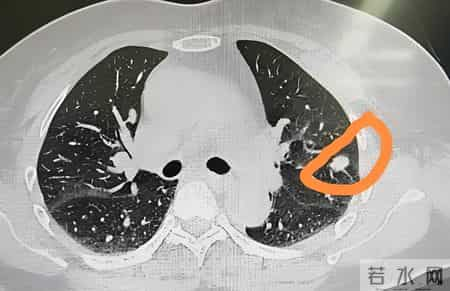

再说说“蒲公英可以消除结节”的说法。这也是很多人关心的问题,尤其是中老年人在体检时经常会被告知“有个小结节”,不管是肺部、甲状腺还是乳腺,听到“结节”两个字,立马就慌了。

但真有这么简单吗?医学上讲,结节只是一个影像学描述,并不等同于疾病。它可能是良性的,也可能是恶性的;可能是慢性炎症引起的,也可能是增生、钙化、纤维化的表现;有的结节几年都不变,有的则需要进一步检查甚至处理。

所以如果你体检发现有结节,最靠谱的做法还是:听医生安排,定期复查,有需要就进一步检查,千万别自己喝草药“赌一把”。